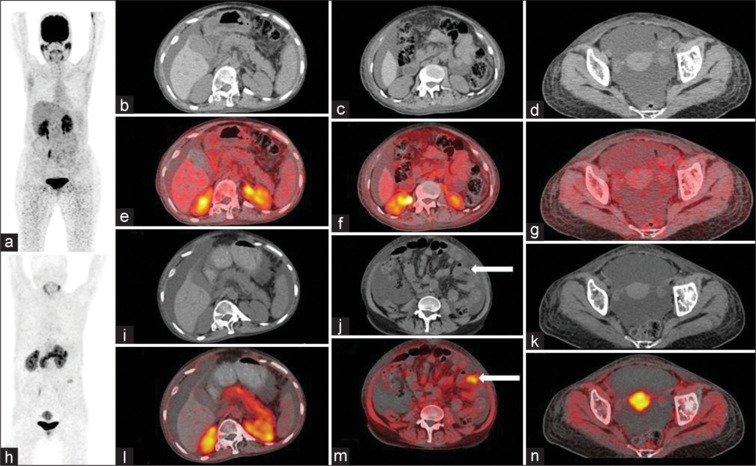

Chylous ascites, attributed to various etiologies including malignancy, tuberculosis, ruptured lymphatics, and congenital lymphatic disorders, manifests as abdominal distension. Our patient presented with this condition, and an elevated CA 125 prompted further investigation. Flourine-18 fluorodeoxyglucose positron emission tomography/computed tomography (PET-CT) revealed a metabolically inactive omental nodule, while gallium 68 fibroblast activation protein inhibitor (Ga-68-FAPI) PET-CT demonstrated uptake in the same nodule and low-grade uptake in bilateral adnexae. Colloid liver scan ruled out chronic liver disease. Surprisingly, lymphoscintigraphy showed no lymphatic leak. Histological examination of the omental nodule confirmed heterotopic pancreas (HP) in the small bowel mesentery, with normal adnexae. This case report illuminates the diagnostic challenges entailed in HP and signifies a pioneering instance in the literature where evidence of HP was identified for the first time on Ga-68-FAPI PET-CT during the investigative process.